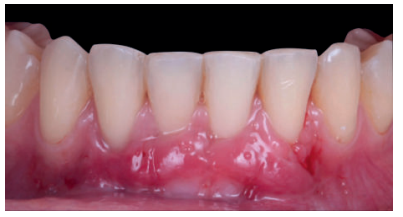

Se realizó control a la semana de la intervención (Figura 4) y tras 15 días se retiró la sutura, observando la revascularización del injerto y la epitelización del área cruenta apical al sobre (Figura 5). Se realizó seguimiento al mes (Figura 6), a los 3 meses (Figura 7) y al año y medio del procedimiento (Figura 8).

El control a la semana (Figura 13) presentaba inflamación moderada y a las 2 semanas (Figura 14) se retiraron los puntos de sutura. La paciente acudió a los 4 meses (Figura 15) y al año (Figura 16) a visitas de revisión, donde se apreció una buena banda de tejido queratinizado y una pequeña cicatriz.